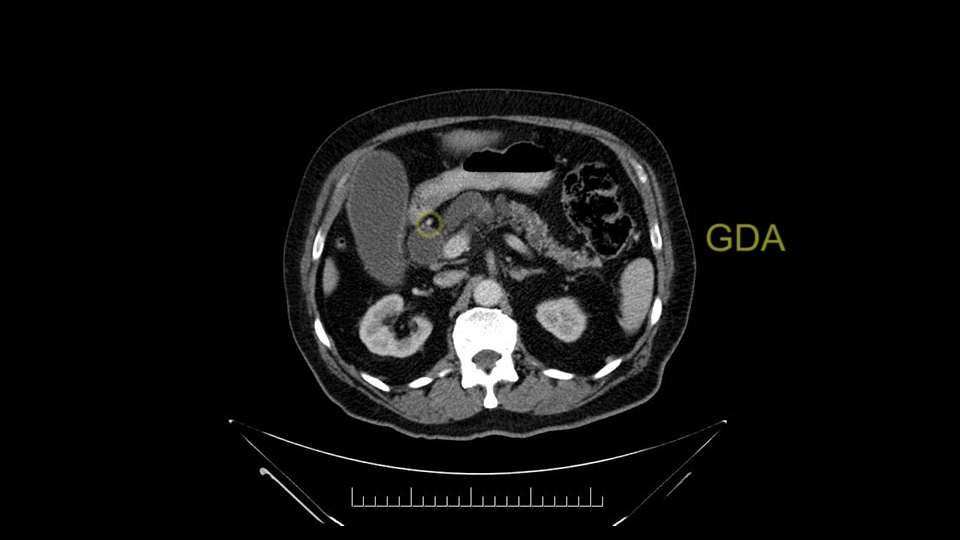

The gastroduodenal artery, a major artery that we have to divide, along with some pancreatoduodenal arteries, may have atherosclerotic changes so they would have to be handled with care, when I attempt what I think would be a pylorus-preserving pancreatoduodenectomy would be the plan. In some cases, I might make an intraoperative change and do a partial antrectomy or a pylorus-resecting Whipple, should the need arise for technical reasons but not because of the size of the tumor.

The other slowing down moment would be the gastroduodenal artery. Confirming that the gastroduodenal artery is not a dominant artery supplying blood to the liver. Liver failure is something which we don’t want due to altered blood supply to the liver or hampered arterial blood supply to the liver. So I would dissect out the hepatic artery, the left and right branches very clearly. Put a bulldog clamp on the gastroduodenal artery, make sure that the perfusion of the liver is excellent on the right and left side, and then divide the gastroduodenal artery. I would avoid using crushing instruments or crushing clamps on the gastroduodenal artery because they have a tendency to shatter in patients who are old with friable vessels so you have to be careful and tackle it with the help of a 5-0 or a 6-0 prolene sutures. In younger patients, I would just apply clips and move on when it comes to dividing the gastroduodenal artery.

First, the stenosis of the celiac trunk, which can be caused by arteriosclerosis, especially in a patient who is 83, or in patients who have arcuate ligament; we do see it, sometimes in much younger patients. In those cases, it may be that the circulation of the hepatic artery comes entirely from the gastroduodenal artery and its anastomoses, through the pancreaticoduodenal arteries, coming from the superior mesenteric artery. This means that before the gastroduodenal artery is ligated, we first clamp and wait 30 seconds to a minute, to feel and check the arterial inflow to the liver. If the pulse is diminished or there is a complete absence of the pulse, the surgery should be modified or probably a pancreatoduodenectomy cannot be done, because of the risk - when ligating the gastroduodenal artery - of causing fulminant hepatic ischemia postoperatively.

I am a believer in pylorus preservation. And in this case I see no reason why that wouldn't be possible. Mobilize the duodenum, divide the gastroepiploic vessels and divide the duodenum. I try to divide it with a linear stapler about four centimeters from the pylorus to have adequate length for my GI anastomosis. This facilitates exposure of the head neck of the pancreas. I find the gastroduodenal artery. This patient has normal arterial anatomy. Always on every preoperative CT scan I look to see if there is a replaced right hepatic. In this case I did not see one. Regardless of how confident I am I always look carefully for variant anatomy. I always do a clamp test on the GDA before ligation. I doubly ligate the GDA with not just a tie but a suture ligature because of the risk of GDA blowout in patients with a leak.